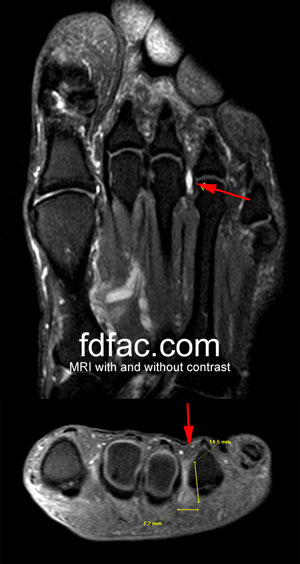

Neuroma Pain

Reader Doug writes “I have been having trouble maintaining a level of consistency in my training due a Morton’s Neuroma in my left foot. Over the past two years, I have had 2 cortisone shots, switched shoes multiple times to different sizes, widths, and makes. The first time I had a neuroma, I was running in the Brooks Adrenaline GTS 8 in a size 9 regular width. Then I switched to the Asics GT-2150 size 8.5 2E width.”

Doug is not alone in his frustration of not being able to solve his neuroma pain by changing his shoes. Unfortunately, even with shoe changes or orthotics, neuroma pain can continue to worsen.

A neuroma is an inflamed nerve in the forefoot. Symptoms include burning and tingling in the toes, or feelings of walking on a bunched-up sock. For some people, the discomfort is more noticeable while wearing shoes, for others the discomfort is more pronounced when barefoot. For everyone, however, the more frequent and the longer the symptoms persist, the worse the prognosis.

When this happens, treatment recommendations include cortisone injections and medical grade alcohol, or sclerosing injections infiltrated into and around the nerve.

When a neuroma doesn’t respond to cortisone or sclerosing injections, surgery is the next likely step. To locate a qualified foot and ankle surgeon see http://www.acfas.org/